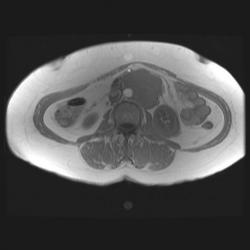

Женщина 47 лет, в течении долгого времени страдала от головных болей. В последние несколько месяцев - прогрессирующая потеря зрения (на оба глаза).

Случай "учебный", и сложностей не должен представлять.

Presented images are corresponded for cerebral (right temporal-occipital region) neoplasia; high grade glioma is most suggested.

Глиальная опухоль.